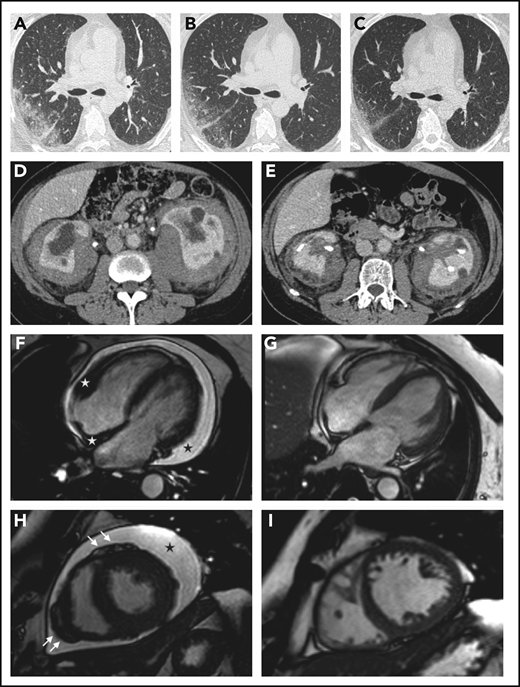

Organ responses. (A-C) Chest high-resolution CT scans in patient 12 show progressive regression of ECD-related lung disease (the scans were taken respectively before treatment and at months 6 and 12 after the beginning of therapy with everolimus) (axial view). (D-E) Contrast-enhanced abdominal CT scans in patient 8 show marked regression of perirenal infiltration with consequent improvement of hydronephrosis and calycectasia (axial view). (F-I) Cardiac magnetic resonance (cine frame from steady-state free precession sequence) in a patient (#19) with cardiac involvement; the scans were taken at baseline (F,H) and after 1 year of treatment (G,I). (F) Circumferential pericardial effusion (black star) and pathologic soft tissue in the right atrioventricular groove and the right side of the interatrial septum (white stars). Arrows (H) indicate nodular thickening of the visceral pericardium. Pericardial effusion and infiltrative lesions almost completely disappeared (G,I; scans after treatment).

The best objective responses were observed at the retroperitoneal, cardiac, and large-vessel levels. Retroperitoneal lesions partially or completely regressed in 9 out of 17 patients (53%) and stabilized in 7 patients. Two of the 3 patients who underwent ureteral stenting became stent-free. Cardiac lesions partially regressed on MRI in 6 out of 8 patients (75%). Six patients remained free of pericardial effusion over the entire follow-up, whereas patient 10 progressed. Large-vessel lesions improved in 11 out of 14 patients (79%).

Bone disease remained stable or slightly improved on bone scintigraphy in all patients. CNS lesions partially regressed in 2 out of 6 patients (33%), stabilized in 3 patients, and progressed in 1 patient (#18). Lung involvement improved in 2 out of 6 patients and stabilized in 2 patients; patient 14 died of pulmonary involvement (supplemental Table 2).